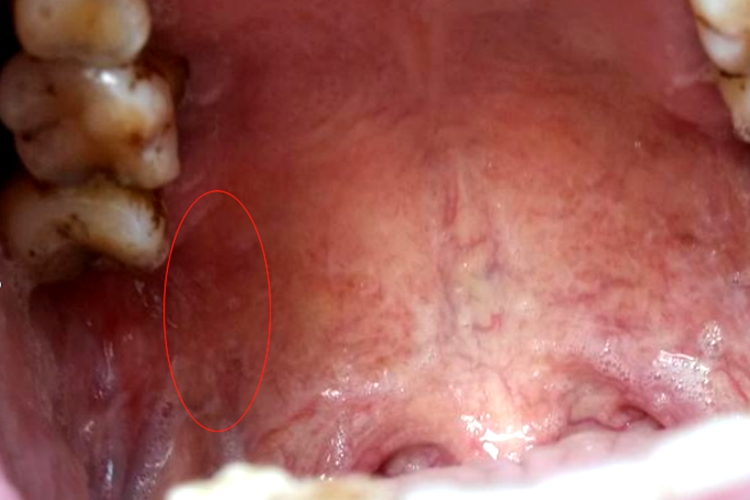

口腔上颚有个凸起肉粒可有多个,呈波纹状,也可表现为局部单个小水泡等表现。

正常生理结构:如腭皱襞,为上腭中缝前部向两侧略呈波纹状的黏膜皱襞,外观可呈凸起肉粒状。

慢性根尖周炎:一般无明显的自觉症状,有的患牙可在咀嚼时有不适感。如发生在上牙的病症,则可因牙龈部位的病变波及周围组织而导致上腭的腭皱襞肿胀,则可呈现凸起肉粒。

疱疹性咽峡炎:可在上腭部,尤其是软腭部出现散在数枚灰白色小疱,可呈凸起肉粒,直径为1-2mm,周边有红晕,逐步破溃呈黄色溃疡。